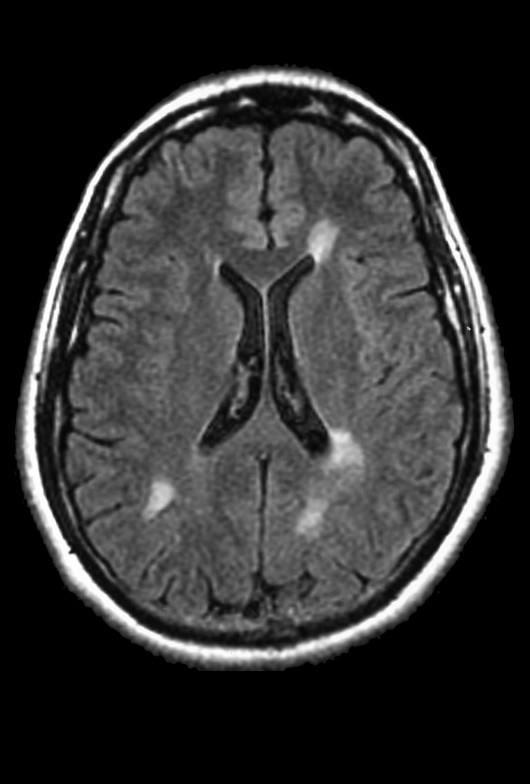

MAGNETNA REZONANCA (MRI)

Magnetna rezonanca najvažnija je neuroradiološka metoda u dijagnostici multiple skleroze.

Na MRI snimkama mogu se uočiti demijelinizacijski plakovi u bijeloj tvari mozga i kralježnične moždine.

Važno je razlikovati nalaz multiple skleroze od tzv. klinički izoliranog sindroma, koji predstavlja samo jednu kliničku manifestaciju s jednom izoliranom demijelinizacijskom lezijom.

MRI je vrlo osjetljiva metoda koja također omogućuje isključivanje drugih bolesti koje mogu oponašati simptome multiple skleroze.

U akutnoj fazi bolesti mogu se koristiti kontrastna sredstva koja omogućuju bolje prikazivanje aktivnih upalnih lezija.

U liječenju multiple skleroze trenutačno se najčešće primjenjuju interferoni beta skupine. Interferone beta odobrila je i preporučila Američka agencija za hranu i lijekove (FDA), jer su se pokazali učinkovitima u smanjenju egzacerbacija relapsno-remitentnog oblika bolesti te u smanjenju patoloških promjena vidljivih na MRI snimkama. Pozitivni učinci zabilježeni su i kod sekundarno progresivnog oblika, gdje značajno usporavaju progresiju bolesti.